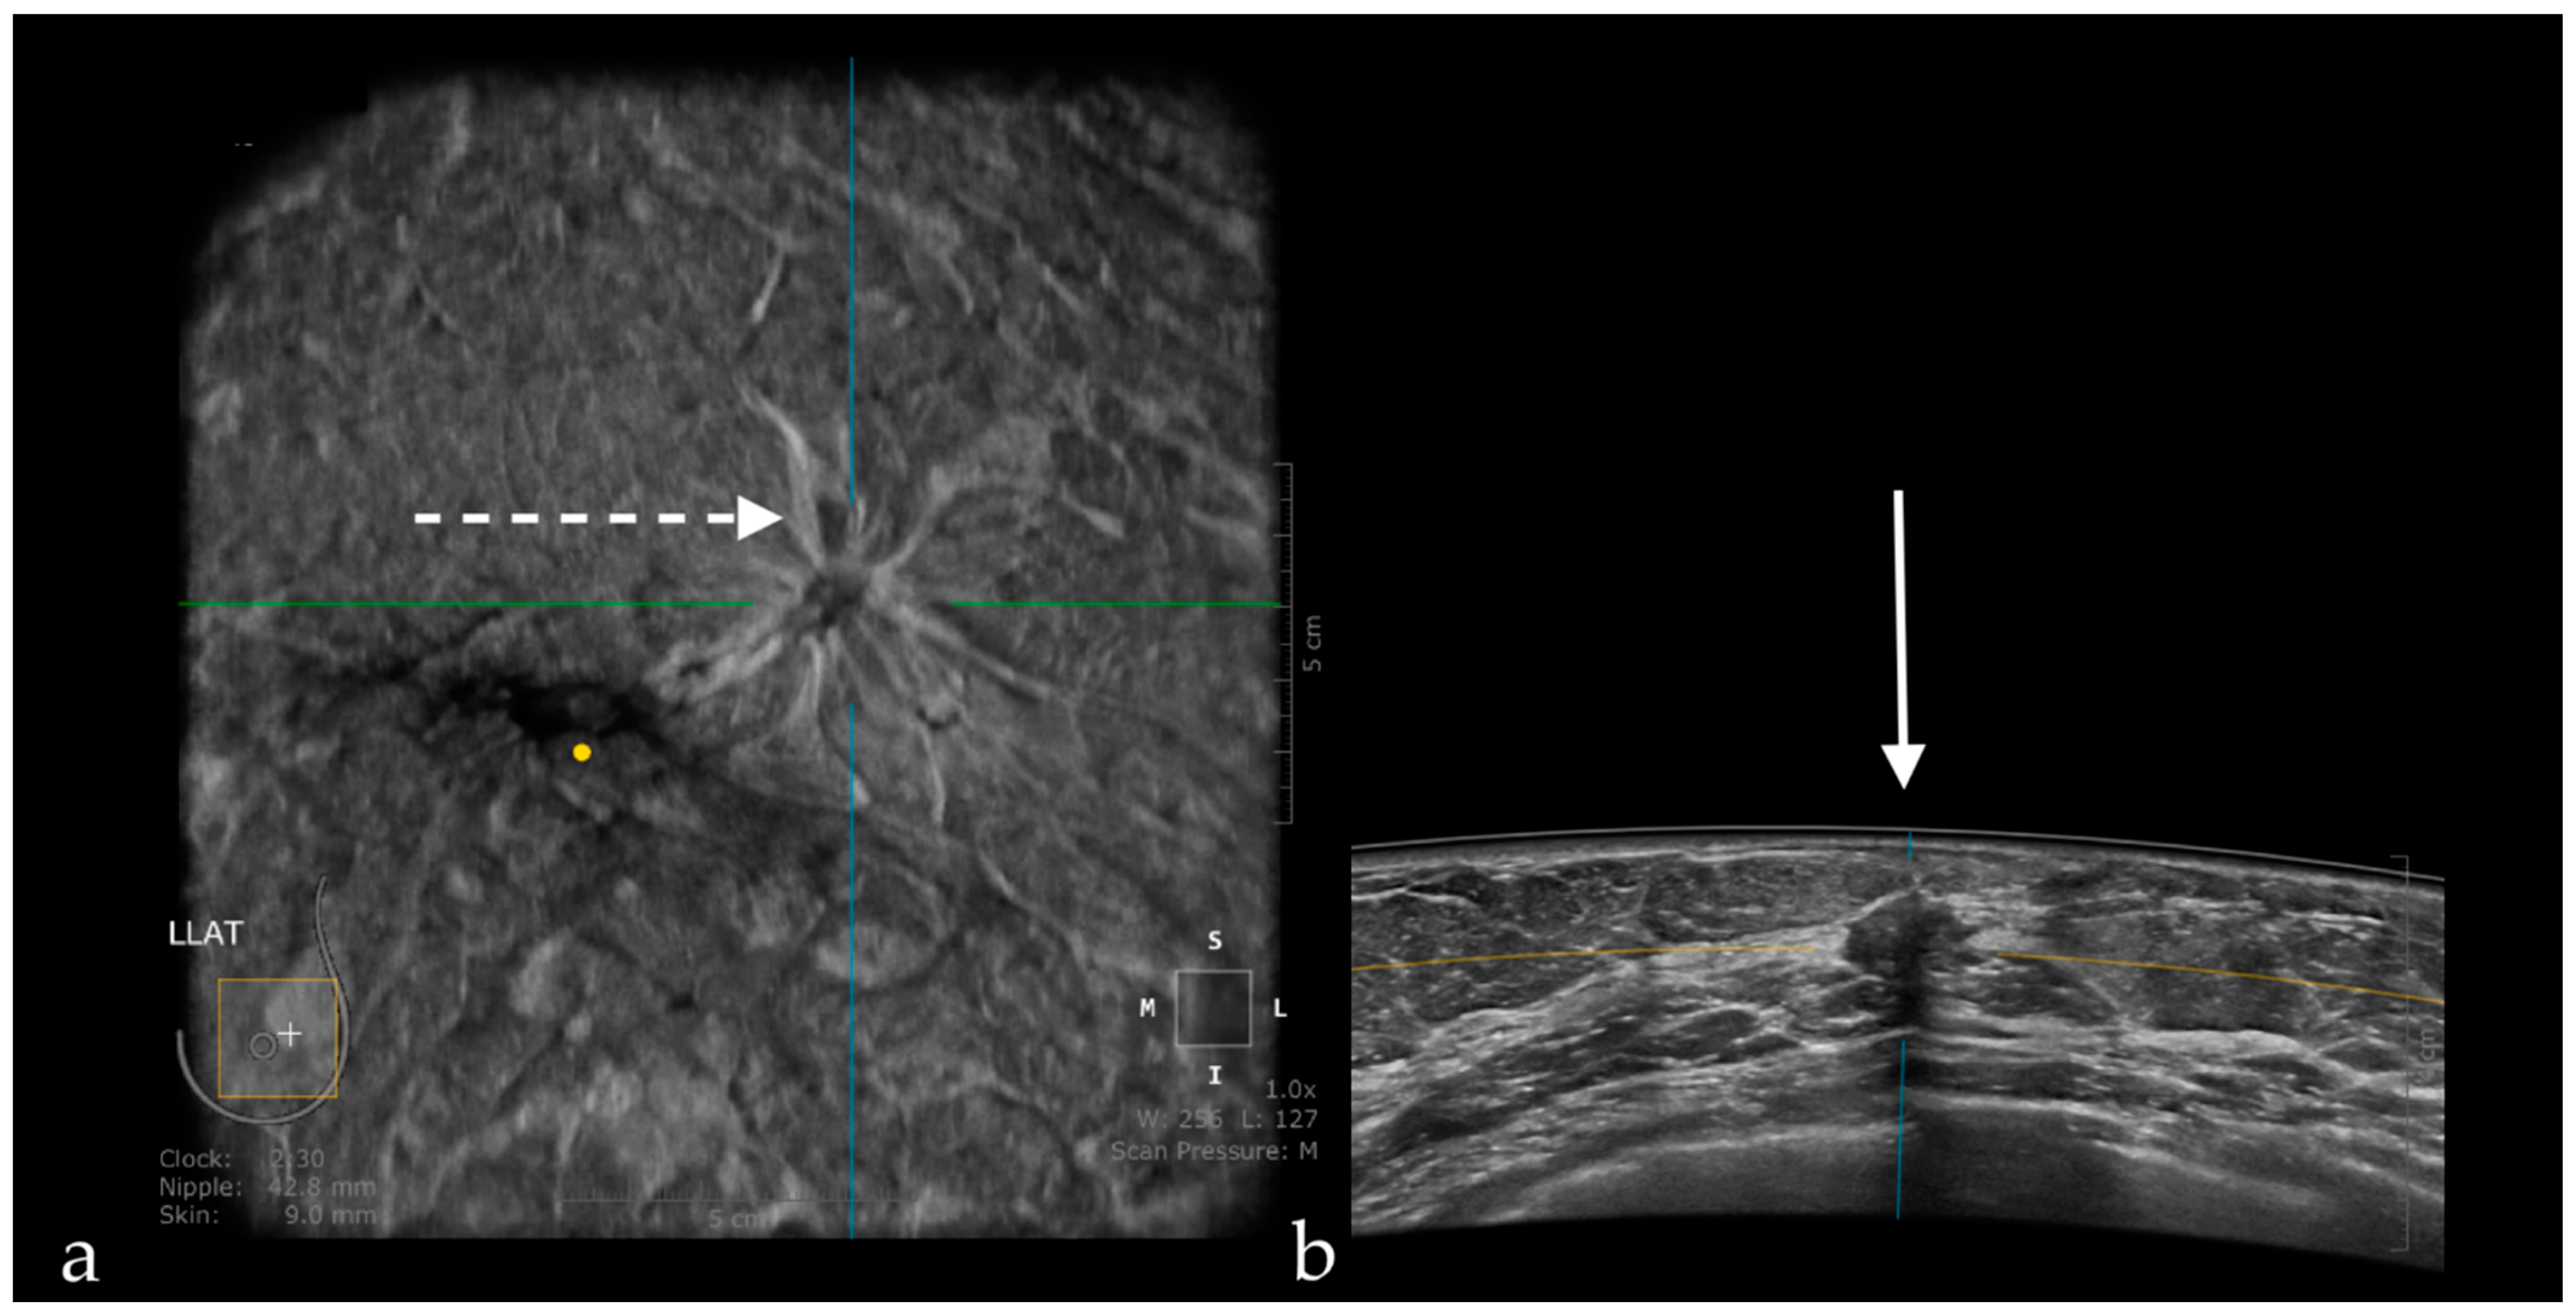

The Usefulness of the Coronal Plane

- Zheng, F.Y.; Yan, L.X.; Huang, B.J.; Xia, H.S.; Wang, X.; Lu, Q.; Li, C.X.; Wang, W.P. Comparison of retraction phenomenon and BI-RADS-US descriptors in differentiating benign and malignant breast masses using an automated breast volume scanner. Eur. J. Radiol. 2015, 84, 2123–2129. [Google Scholar] [CrossRef] [PubMed]